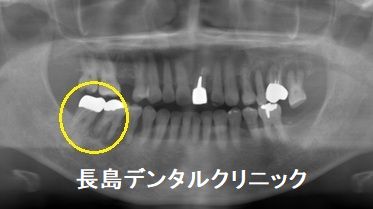

1、インプラント埋入前

患者様は顎の骨が太く、噛む力が強い方です。歯周病に罹患した原因

(黄色い丸印)の一つにはその力の可能性があります。このような方

には細いインプラントをなるべく骨深くに埋入するよりも、短くても

いいですから、なるべく径の太いインプラントを選択したほうが、噛

む力をしっかり支えてくれて、それはインプラント周囲の骨が吸収す

るインプラント周囲炎のリスクを軽減します。